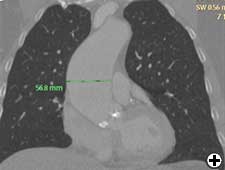

Ascending aorta dilatation should be confirmed with CT scan, aortography, or TOE.

- Choose an appropriate diameter Dacron tube graft, for example, 1.5-2 cm less the diameter of ascending aorta. In this patient we used 3.8 cm Dacron tube graft when proximal and distal ascending aorta were 5.4 cm and 5.69 cm respectively on preoperative TOE (Figures 3 & 4).